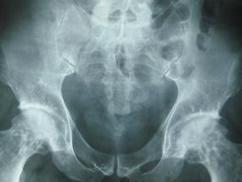

骨软骨病是一种关节软骨和骺软骨软骨内骨化障碍的非炎性疾病。临床上常见的骨软骨病有如下几种:①分离性骨软骨病;②肘突不闭合;③尺骨冠状突分裂;④骺生长板骨化迟滞。